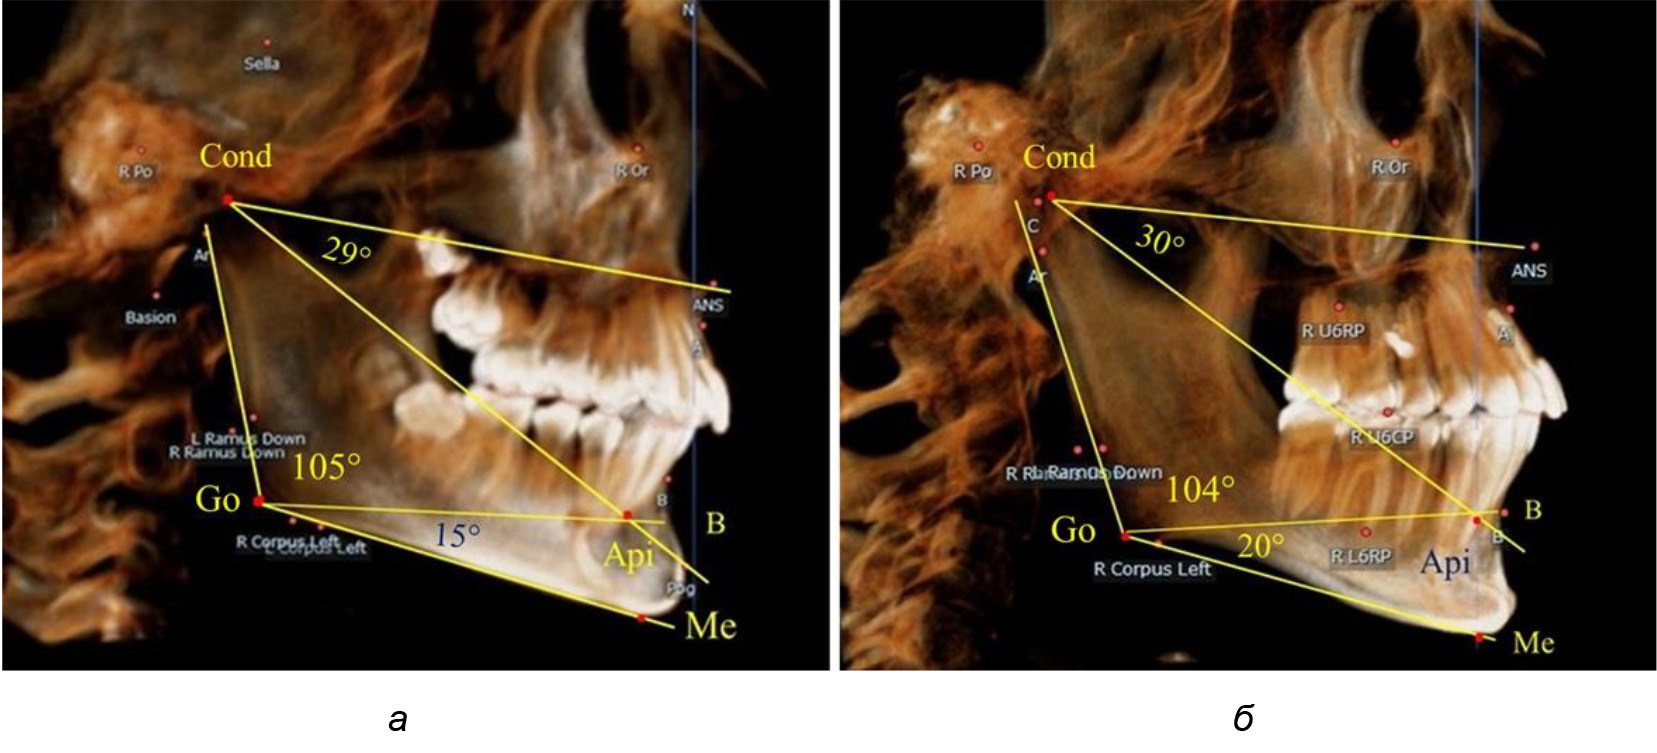

Таким образом, в периоде молочного прикуса с оптимальными окклюзионными соотношениями, несмотря на линейные размеры в вертикальном и сагиттальном направлении, которые, безусловно, меньше параметров взрослых людей, величина основного угла гнатической части лица SNA-Cond-Api соответствовала параметрам людей с полностью сформированным физиологическим прикусом постоянных зубов. Анализируя данные рентгенограмм детей в периоде сменного прикуса, отмечено, что величина основного угла гнатической части лица SNA-Cond-Api, так же как в молочном и постоянном прикусе, в норме составляла от 28 до 32°. В то же время угол нижней челюсти и его составляющие отличались вариабельностью параметров при различных показателях нижнечелюстного угла. Достоверных различий угла гнатической части после смены нижних медиальных резцов и прорезывания первых постоянных моляров (4 ребенка) не было; происходил очередной этап подъема высоты прикуса и увеличение линейных размеров костей гнатической части, однако угловые параметры были относительно стабильны. После смены всех резцов и замены первых молочных моляров первыми премолярами (6 человек) увеличивались линейные размеры при сохранившихся угловых показателях гнатической части лица (рис. 5).

Рис. 5. Варианты ТРГ после прорезывания ППМ и нижних резцов (а), всех резцов и первых премоляров (б)

Таким образом, в период сменного прикуса с оптимальными окклюзионными соотношениями, несмотря на увеличение линейных размеров в вертикальном и сагиттальном направлении, по сравнению с прикусом молочных зубов, величина основного угла гнатической части лица SNA-Cond-Api соответствовала показателям как постоянного, так и молочного прикуса с физиологическими окклюзионными соотношениями.